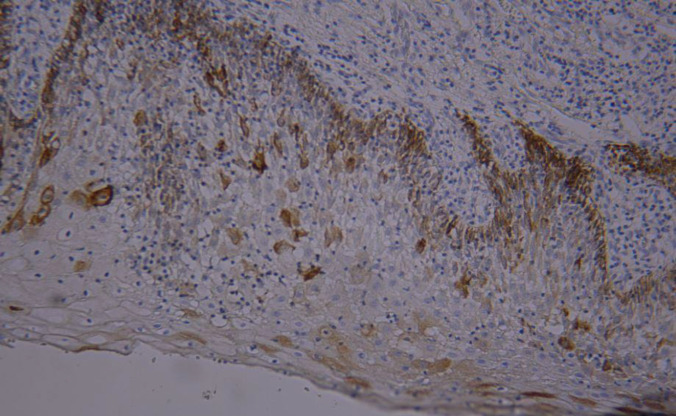

Methods: A total of 50 samples were analyzed, including 30 OSCC cases and 10 OED cases obtained from the archives of the Department of Pathology, as well as 10 normal oral mucosa samples collected from clinically healthy areas adjacent to mucocele lesions. CK19 expression was assessed using immunohistochemistry.

Results: Positive immunoreactivity for CK19 was observed in 90% (27/30) of OSCC samples. CK19 expression in the OSCC group was significantly higher compared to the OED and normal mucosa groups. Among OSCC cases, grade III tumors exhibited stronger CK19 expression than grades I and II. Additionally, CK19 expression in grade II OSCC was higher than in the OED group.

Conclusion: The progressive increase in CK19 expression from normal mucosa to OED and OSCC supports its involvement in oral mucosal carcinogenesis. Moreover, higher CK19 expression correlated with increasing tumor grade and decreasing cellular differentiation, suggesting its potential value as a diagnostic and prognostic biomarker in OSCC.